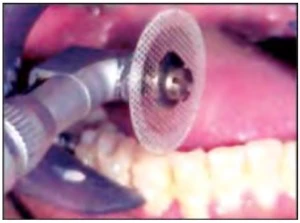

Đĩa kim cương đục lỗ

Đĩa kim cương đục lỗ được sử dụng rộng rãi cho mục đích này. Chúng tương đối mềm dẻo và mài kẽ cả hai răng kế cận nhau.

Hình 1C. Đĩa kim cương đục lỗ